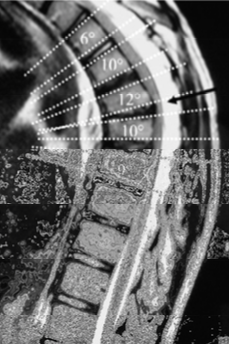

What is Scheuermann’s disease?

A deformity in the thoracic or thoracolumbar spine in children resulting in wedged vertebral bodies and multiple herniations of nucleus pulposus (Smorl’s Nodes)